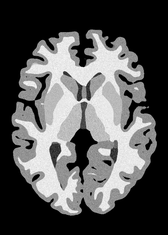

4.2 Registration to a 100 micron ex-vivo brain MRI volume

To showcase the efficacy of our method on real large scale images, we register a 250 in-vivo MRI image (Lüsebrink et al., 2017) to a 100 ex-vivo FLASH human brain volume (Edlow et al., 2019). This represents an inverse problem with more than 11.2B optimizable parameters (compared to 20M for clinical datasets), or 44.8GB of GPU memory. The entire problem does not fit on most GPUs, necessitating distributed multimodal registration. We optimize a composite transform - affine followed by a diffeomorphic mapping; details can be found in Section E.1. Multimodal deformable registration took 58 seconds on 8 NVIDIA A6000 GPUs, which is unprecedented at this resolution. Fig. 6 shows qualitative results, highlighting the ability to register highly detailed structures such as cerebellar white matter; these structures are not visible at macroscopic scales. The resultant advantages of performing registration at this scale can allow researchers to characterize the neuroanatomy at microscopic resolutions and allow morphometric analysis of cortical layers and subcortical nuclei among other structures.